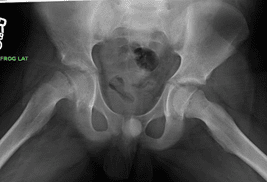

X-ray of stable SCFE

X-ray of an 11-year-old boy with stable SCFE in his right hip.